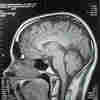

For example, the adrenal glands of all animals have evolved to pump out stress hormones in unexpected situations — the hormones spur action and increase fuel to the brain, helping the animal react to danger appropriately. Those hormones also flow to memory centers in the brain, to help the critter remember those notable moments and places.

"When stress is sustained or repeating or extreme, then all [the usual systems] gets disrupted," says Huda Akil, co-director of the Molecular and Behavioral Neuroscience Institute at the University of Michigan. "And eventually, you do it long enough and it starts impacting other systems ... immune responses; it can affect the heart; it affects brain cells. It depends how long we're talking about."